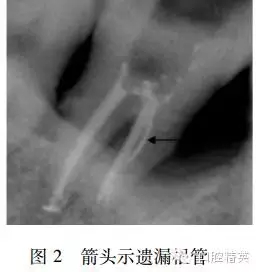

數(shù)字化X線攝影示:7遠(yuǎn)中根根管充填恰填致密,近中遺漏根管(圖2)。去除近中根管內(nèi)回填牙膠,GG鉆擴大根管口,根管顯微鏡下在根管中段偏近中舌側(cè)找到根管口,根管測長,預(yù)備,消毒,試尖(圖3),充填,術(shù)后X線片顯示恰填(圖4)。